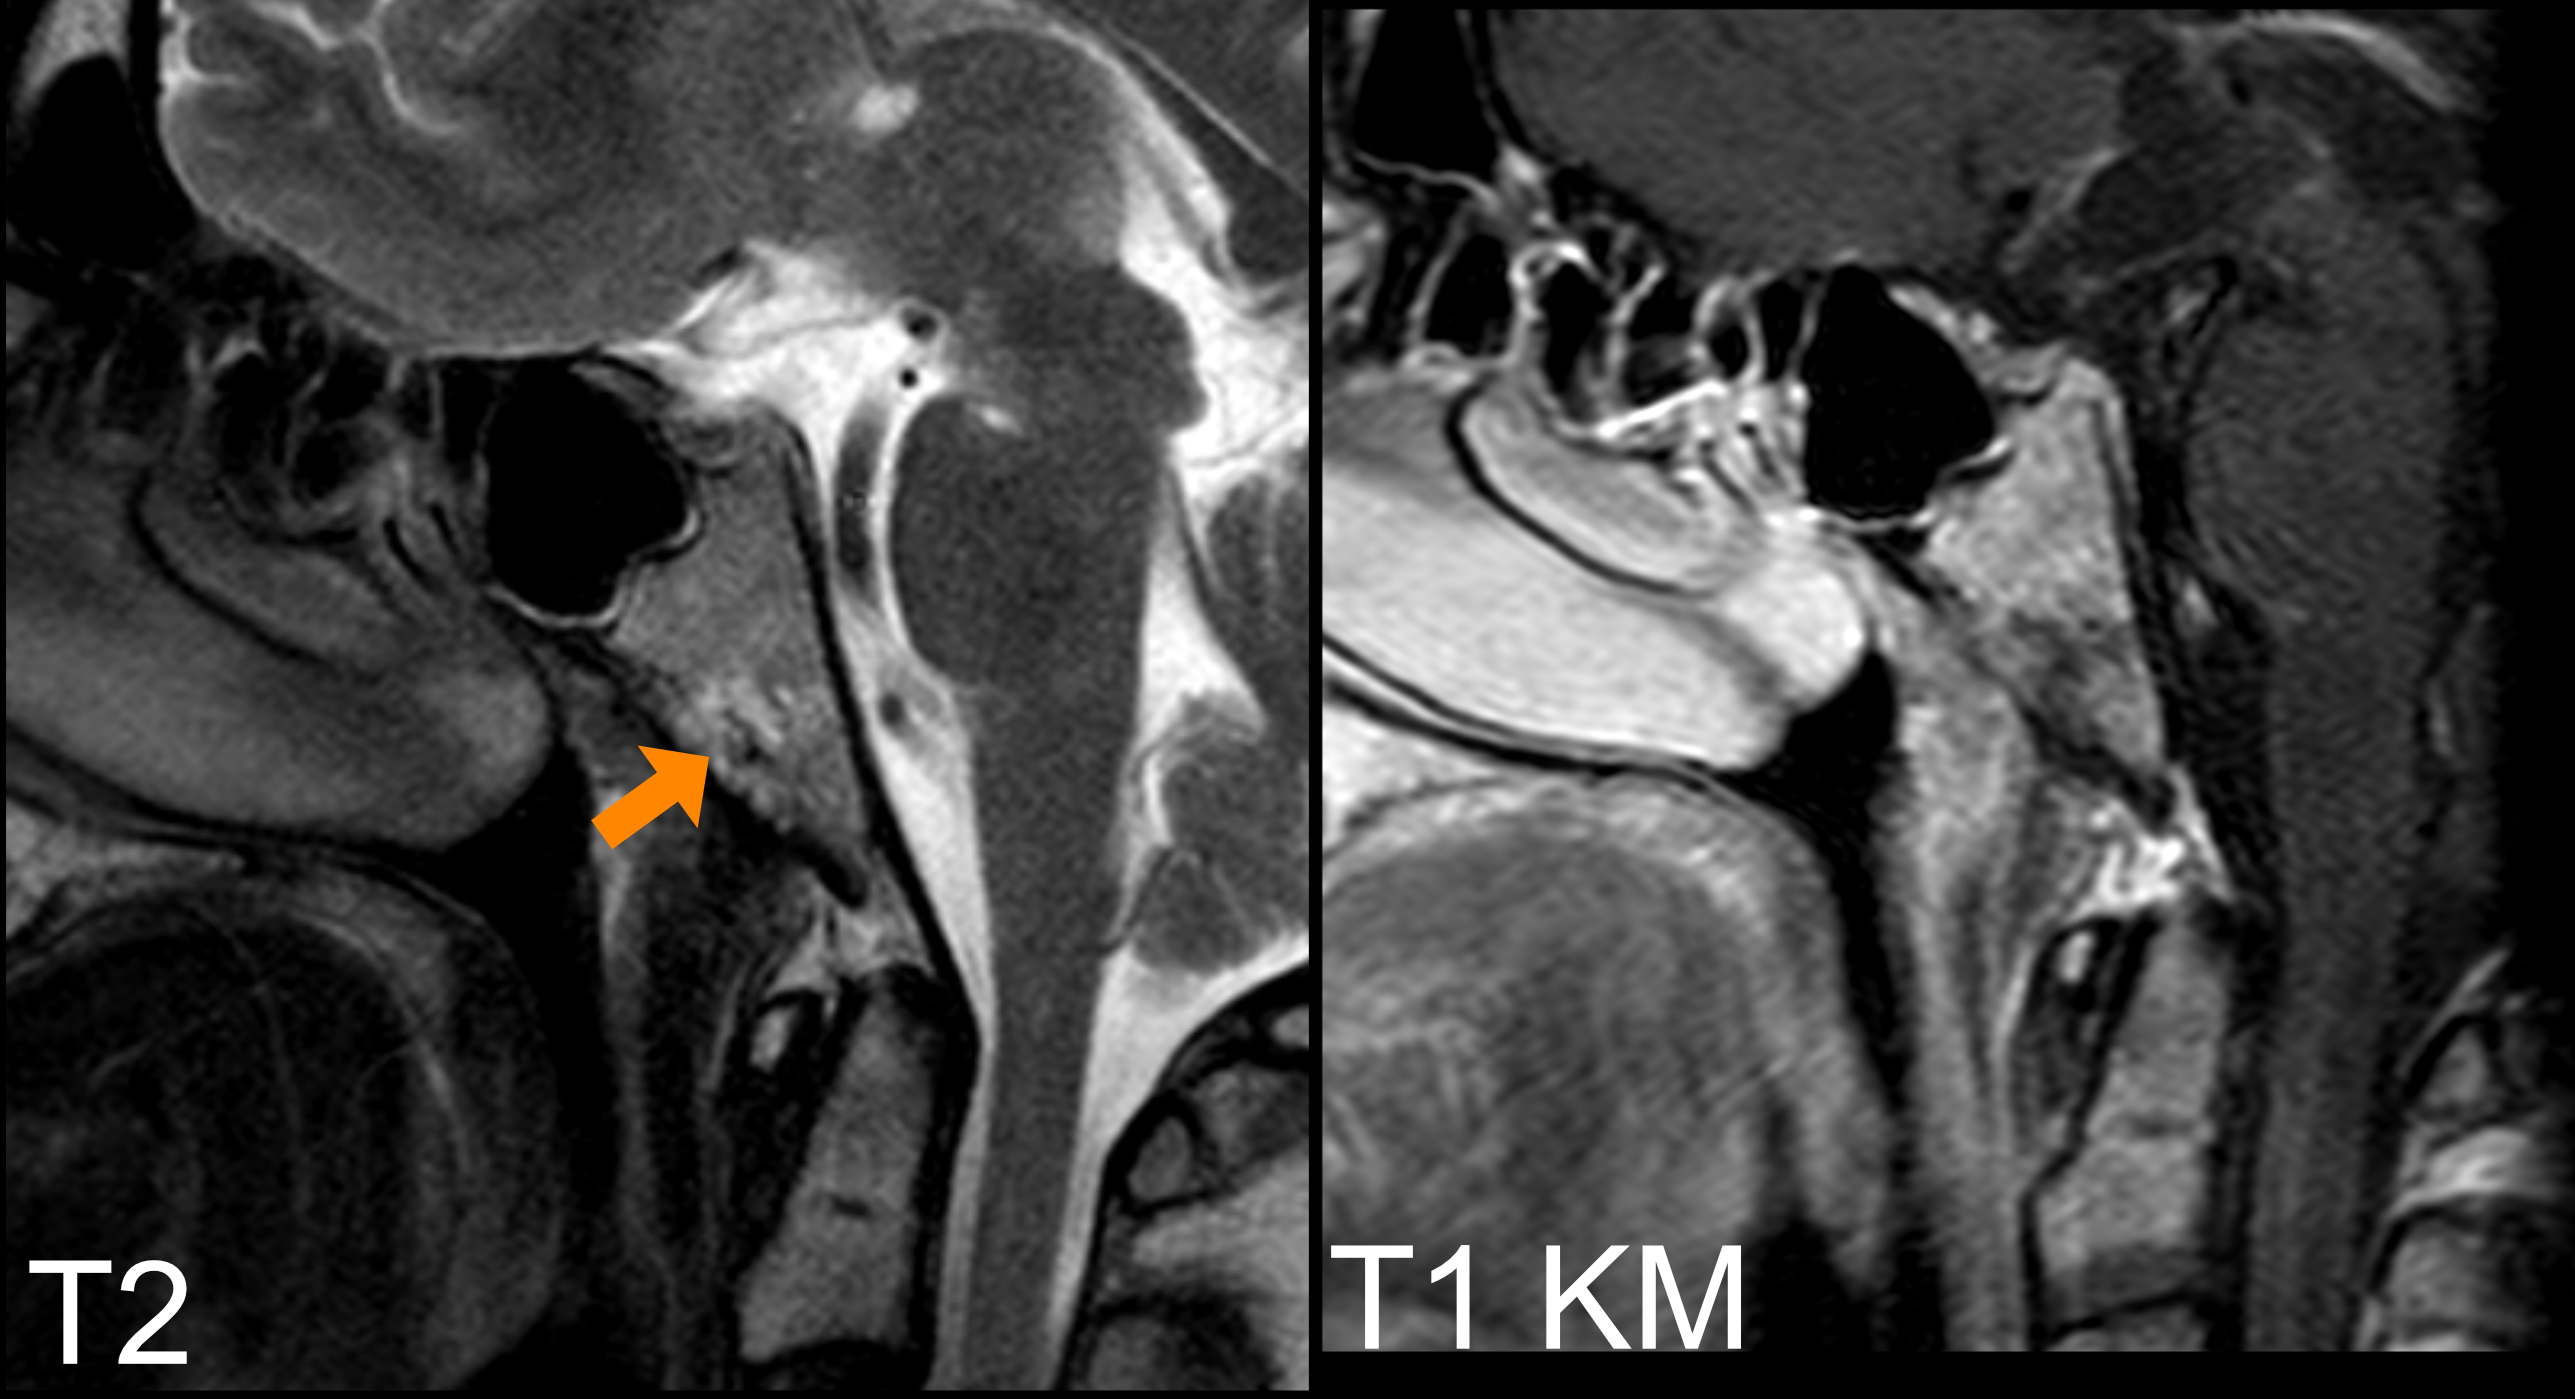

Der Goldstandard bei der Bildgebung von Chordomen ist die MRT-Bildgebung.

MRT

Chordome zeigen sich in der MRT Bildgebung typischerweise wie folgt[^3]:

T1 nativ | T1 mit Kontrastmittel | T2 |

Iso- bis Hypointens | Heterogene Kontrastmittelaufnahme |